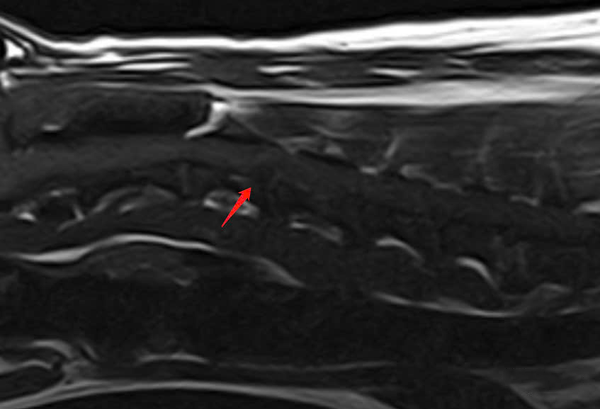

- MRI: Xác định đĩa đệm C3 – C4 thoát vị, chèn ép tủy sống cổ, gây triệu chứng thần kinh.

MRI xác nhận thoát vị đĩa đệm C3 – C4 ra phía sau, biến dạng tủy sống, có tín hiệu T2W cao quanh vùng chèn ép.

Các đĩa đệm cổ khác cũng xuất hiện dấu hiệu mất nước ở nhiều mức độ.